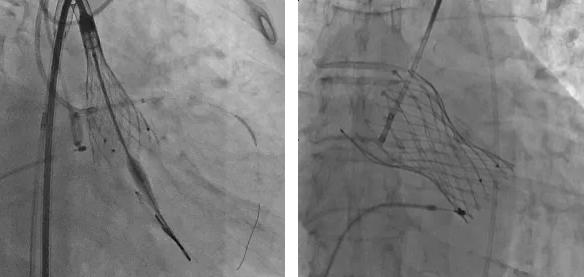

根部造影:瓣葉活動(dòng)度較差,左冠口較低,雙側(cè)冠脈灌注正常,升主動(dòng)脈稍擴(kuò)張。

跨瓣

瓣膜釋放